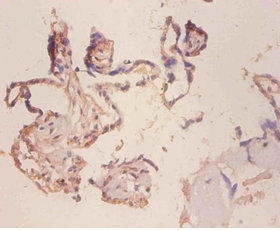

ApplicationELISA, IHC; Recommended dilution: IHC:1:20-1:200